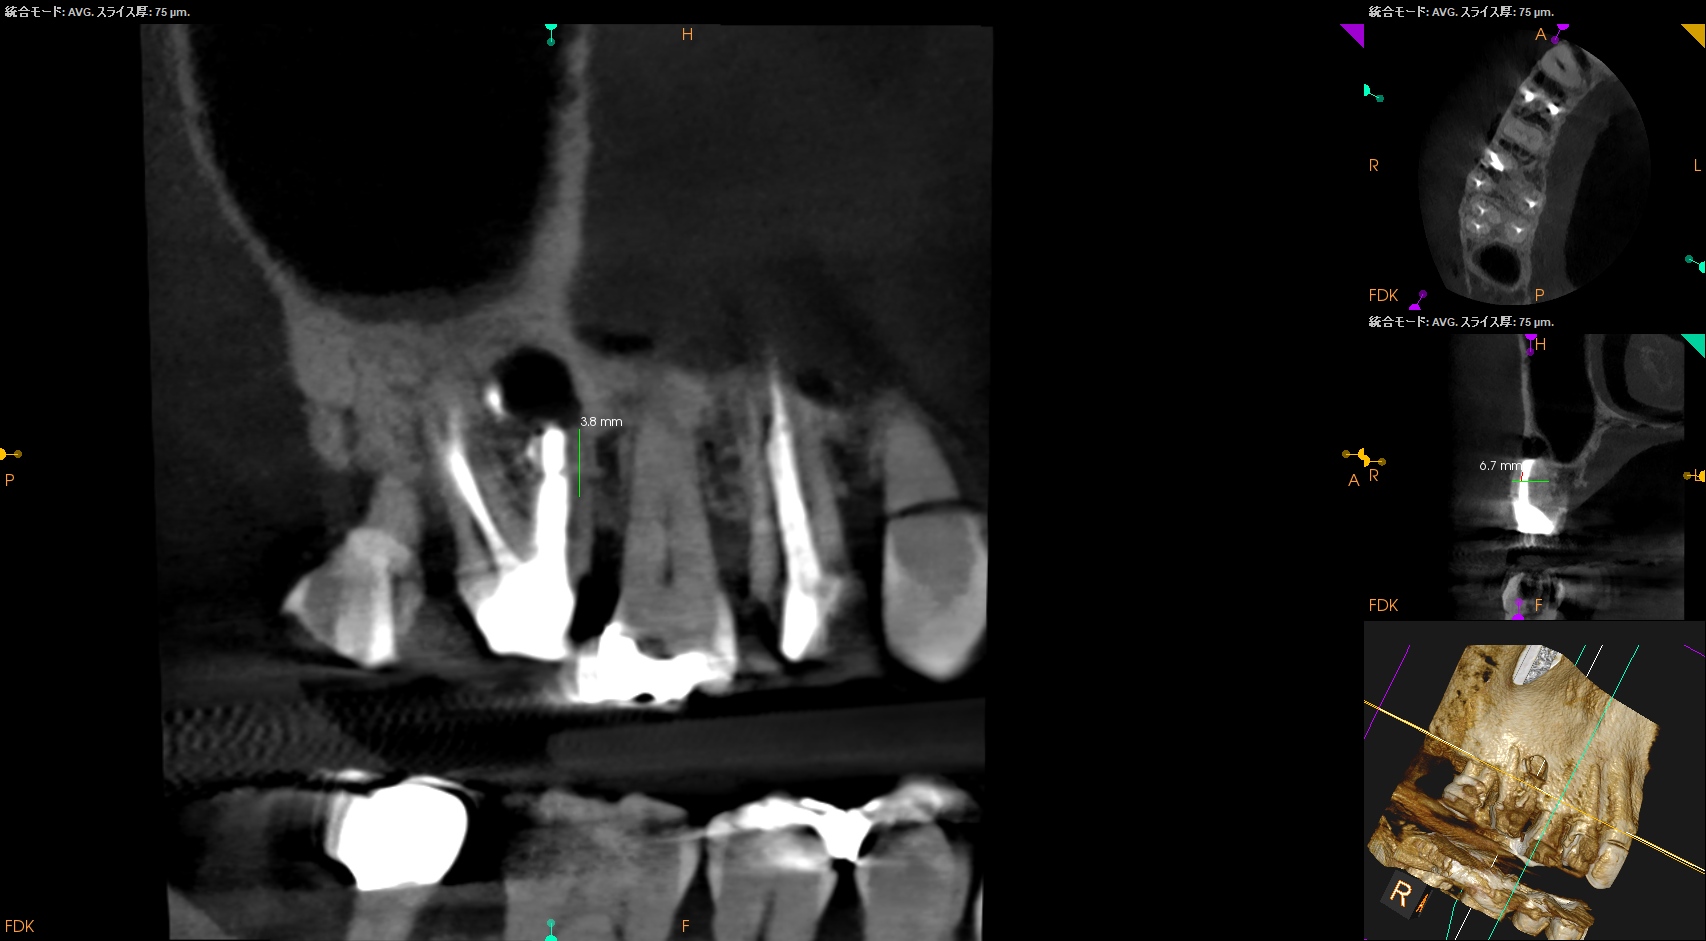

紹介患者さんの治療で、#3 MB Apicoectomyを行ったのだが

MBをRoot resectionした。

ここまでは容易なのだが、この後に逆根管形成・逆根管充填を行うが、

明後日の方向に逆根管形成・逆根管充填してしまう

それだけならばいいのだが、

この状態ではMB2の封鎖がままならない。

つまり、やり直しが必要だ。

その際は、この穿孔部を消去したいので

さらに切断部位から4mm, 頬舌的幅径が6.7mm必要だが再切断し逆根管形成・充填を試みることにした。